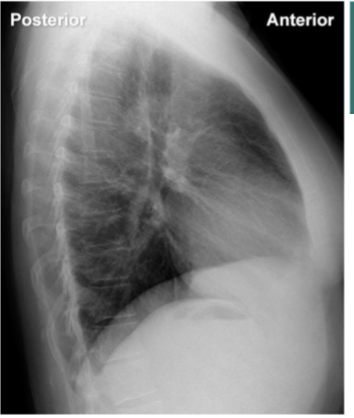

identify hemi diagrams (2) and stomach bubble

yes